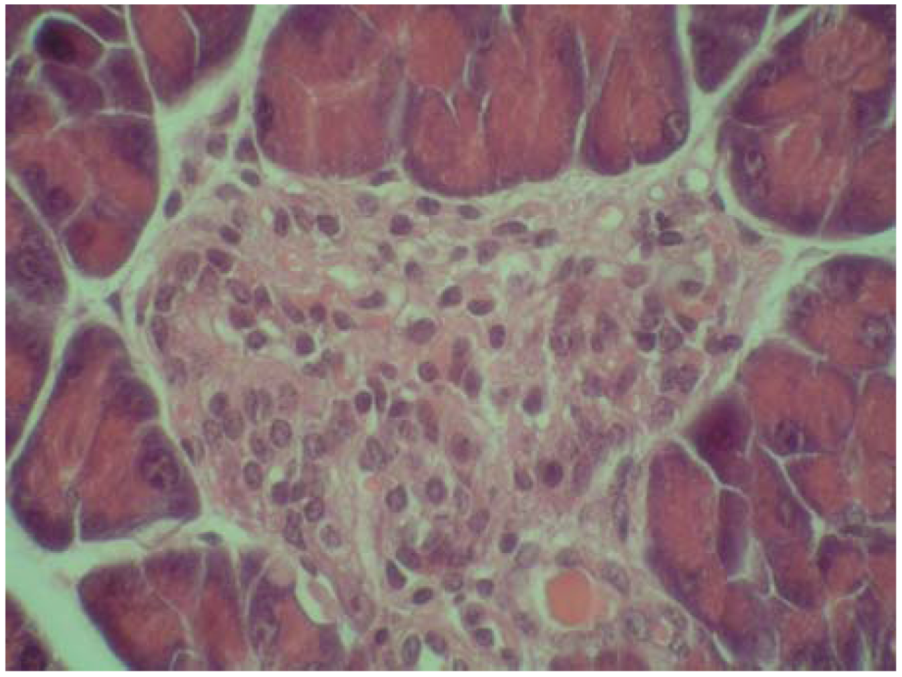

Figure 3.

Microphotograph of the pancreas of alloxan-treated mice (HE 600×). Rudimental reaction to the destroyed pancreatic islet.

On the other hand, some cytoprotective effect of diplacone (1) was proved by histopathological analysis of pancreatic tissue (Figure 2, Figure 3, Figure 4, Figure 5). This observation supports fact that flavonoids may act as a cytoprotective substances [29]. Results of cytoprotective activity assay could be correlated with a higher activity of diplacone (1) compared with the other tested compounds.